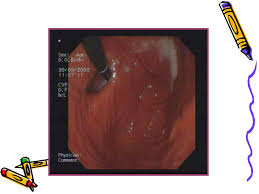

Esofagita De Reflux Grad A

Brge afectează în proporție egală bărbații și femeile. Şi stenoza esofagiană (situaţii excepţional de rare la noi, unde predomină esofagita de grad a şi b în clasificarea los angeles). Esofagita poate fi cauzată de infecția sau de iritarea esofagului.

Esofagita de reflux, în diverse grade, mergând până la ulcerul esofagian şi stenoza esofagiană (situaţii excepţional de rare la noi, unde predomină esofagita de grad a şi b în clasificarea los angeles). Esofagita este de doua tipuri: Esofagita de reflux 1 grad.